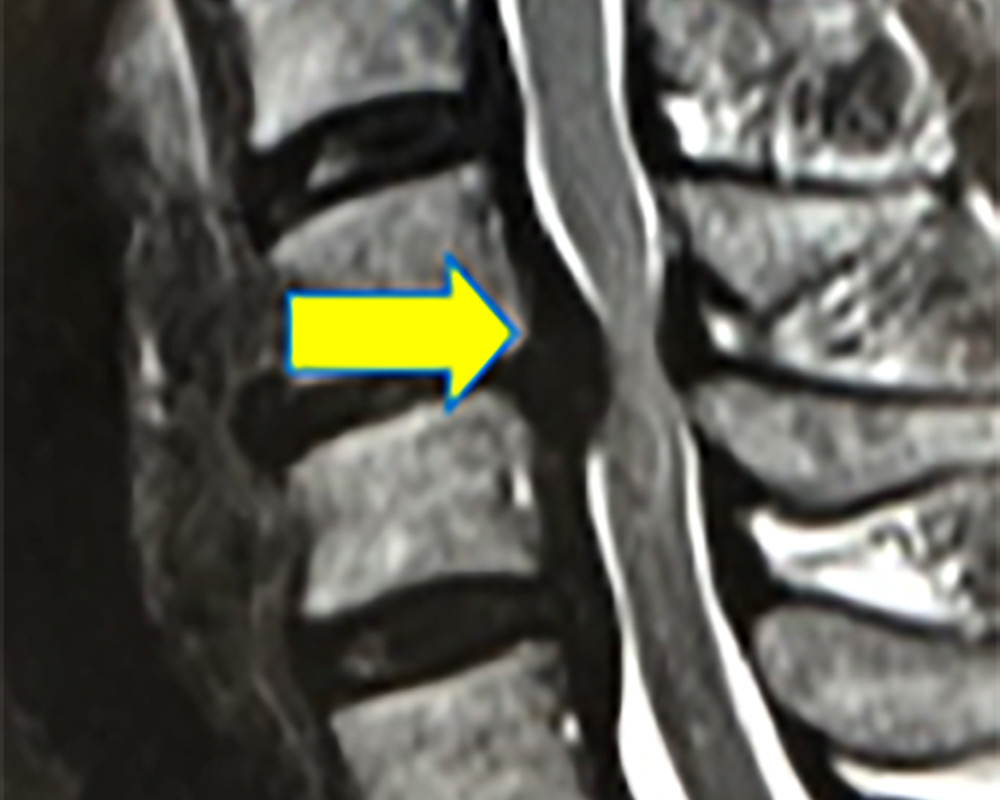

頸椎という首の背骨や椎間板等が変形・変性し、脊髄や神経根が圧迫される事によって、手足の痛みやしびれが出現し、動きが悪くなることのある病気です。頚椎の椎間板が大きく飛び出せば頚椎椎間板ヘルニア(図1)、頚椎の後縦靭帯と呼ばれる膜が骨のように変化すれば頚椎後縦靭帯骨化症、頚椎の骨や椎間板や靭帯が複合的に変形すれば頚椎症といいます。

頚椎椎間板ヘルニアのMRI像

図1 頚椎椎間板ヘルニアのMRI像